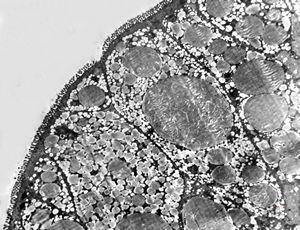

F,8m. | lipid malabsorption - large lipid droplets in enterocytes … semithin section

lipid malabsorption - large lipid droplets in enterocytes … semithin section

lipid malabsorption - large lipid droplets in enterocytes and propria … HE